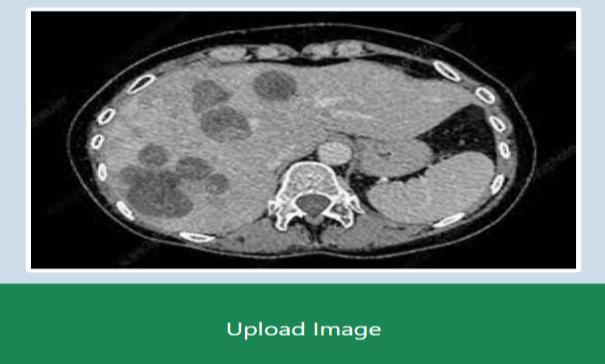

Figure 2 illustrates thepre processing stepsfor liver tumor detection for stage 1. The steps includes the image upload, gaussian filtering, Median filtering, Greyscaling and the binarizedimagewhichisdonethroughthresholding,whose imageisalsoshownbesidethebinarizationattheend.

CT scanned images of Abdomen of stage 1, stage2and stage 3 of liver tumor are used here as input to conduct experimental results. Stage 1 means first stage of liver cancerandStage2meanssecondstageoflivercancerand same goes for stage 3. An comparative analysis graph is being depicted at the end of the results. To show the perfomance comparision between gussian filter and the medianfilter.

Figure 3 illustrates the CT scanimage of abdomen To pre process, initially the data must beselected. By clicking on choose file as shown in home page snapshot, the CT scan image is selected. The bone cancer image data is collected from the liver dataset option in which the database is storedinthefolder.